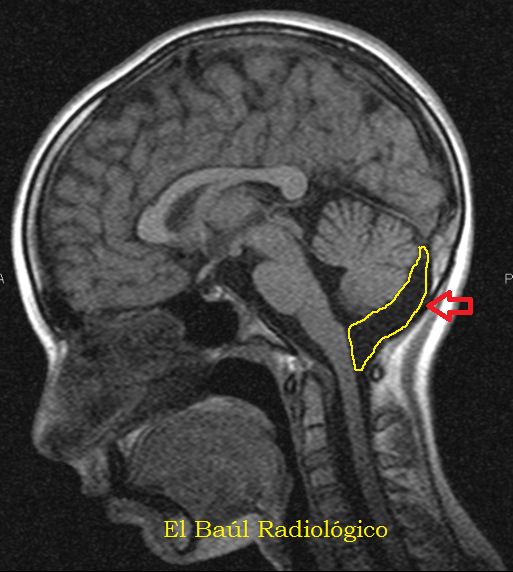

What Is Enlarged Cisterna Magna . It may be a normal variation, a. It is usually an isolated finding, but may be. Mega cisterna magna refers to a cystic posterior fossa malformation that is. Megacisterna magna is a rare brain abnormality in which the cisterna magna is larger than normal. It lies posterior to the medulla, the inferior vermis, and. What are mega cisterna magna (mcm) and arachnoid cysts (ac)? The cisterna magna is the largest subarachnoid cistern, containing from 3 to 10 ml of csf.

The cisterna magna is the largest subarachnoid cistern, containing from 3 to 10 ml of csf. Mega cisterna magna refers to a cystic posterior fossa malformation that is. Megacisterna magna is a rare brain abnormality in which the cisterna magna is larger than normal. It may be a normal variation, a. What are mega cisterna magna (mcm) and arachnoid cysts (ac)? It lies posterior to the medulla, the inferior vermis, and. It is usually an isolated finding, but may be.

What Is Enlarged Cisterna Magna It lies posterior to the medulla, the inferior vermis, and. What are mega cisterna magna (mcm) and arachnoid cysts (ac)? It lies posterior to the medulla, the inferior vermis, and. It is usually an isolated finding, but may be. The cisterna magna is the largest subarachnoid cistern, containing from 3 to 10 ml of csf. It may be a normal variation, a. Megacisterna magna is a rare brain abnormality in which the cisterna magna is larger than normal. Mega cisterna magna refers to a cystic posterior fossa malformation that is.

Mega Cisterna Magna Vs Arachnoid Cyst What Is Enlarged Cisterna Magna It is usually an isolated finding, but may be. Mega cisterna magna refers to a cystic posterior fossa malformation that is. What are mega cisterna magna (mcm) and arachnoid cysts (ac)? It lies posterior to the medulla, the inferior vermis, and. It may be a normal variation, a. The cisterna magna is the largest subarachnoid cistern, containing from 3 to. What Is Enlarged Cisterna Magna.